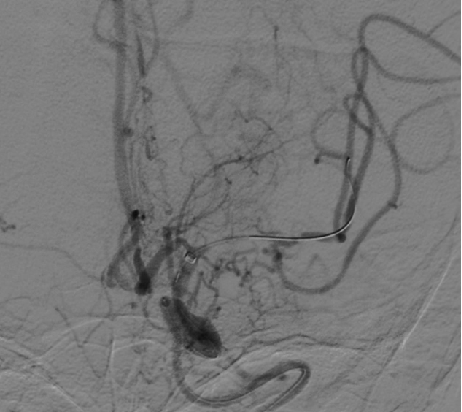

导引导管到位,导丝通过病变。

导丝怎么扩【载药时代 球扩天下】NOVA DES®颅内药物洗脱支架在颅内富穿支区域使用体会二例!_https://www.jmylbn.com_新闻资讯_第14张

导丝怎么扩【载药时代 球扩天下】NOVA DES®颅内药物洗脱支架在颅内富穿支区域使用体会二例!_https://www.jmylbn.com_新闻资讯_第15张

球囊扩张后。